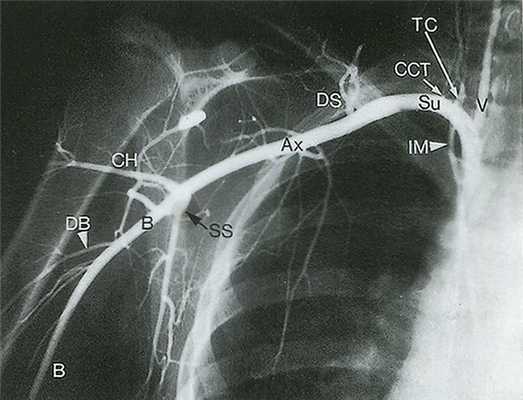

Рис. 14.3. Подключичная артерия (Su) отходит от подмышечной артерии (Ах) на уровне латерального края I ребра. Подмышечная артерия в свою очередь переходит в плечевую артерию (В) на уровне нижнелатерального края большой круглой мышцы. Заслуживают внимания такие ветви подключичной артерии, как щитошейный ствол (ТС) и реберно-шейный ствол (ССТ), поскольку при допплерографическом исследовании они могут быть ошибочно приняты за позвоночные артерии (V). Множественные ветви, кровоснабжающие мышцы лопатки, служат коллатералями при обструкции подключичной артерии или плечеголовного ствола. СН - артерия, огибающая плечевую кость; DB - глубокая артерия плеча; DS - дорсальная лопаточная артерия; IМ - внутренняя грудная артерия; SS - подлопаточная артерия.